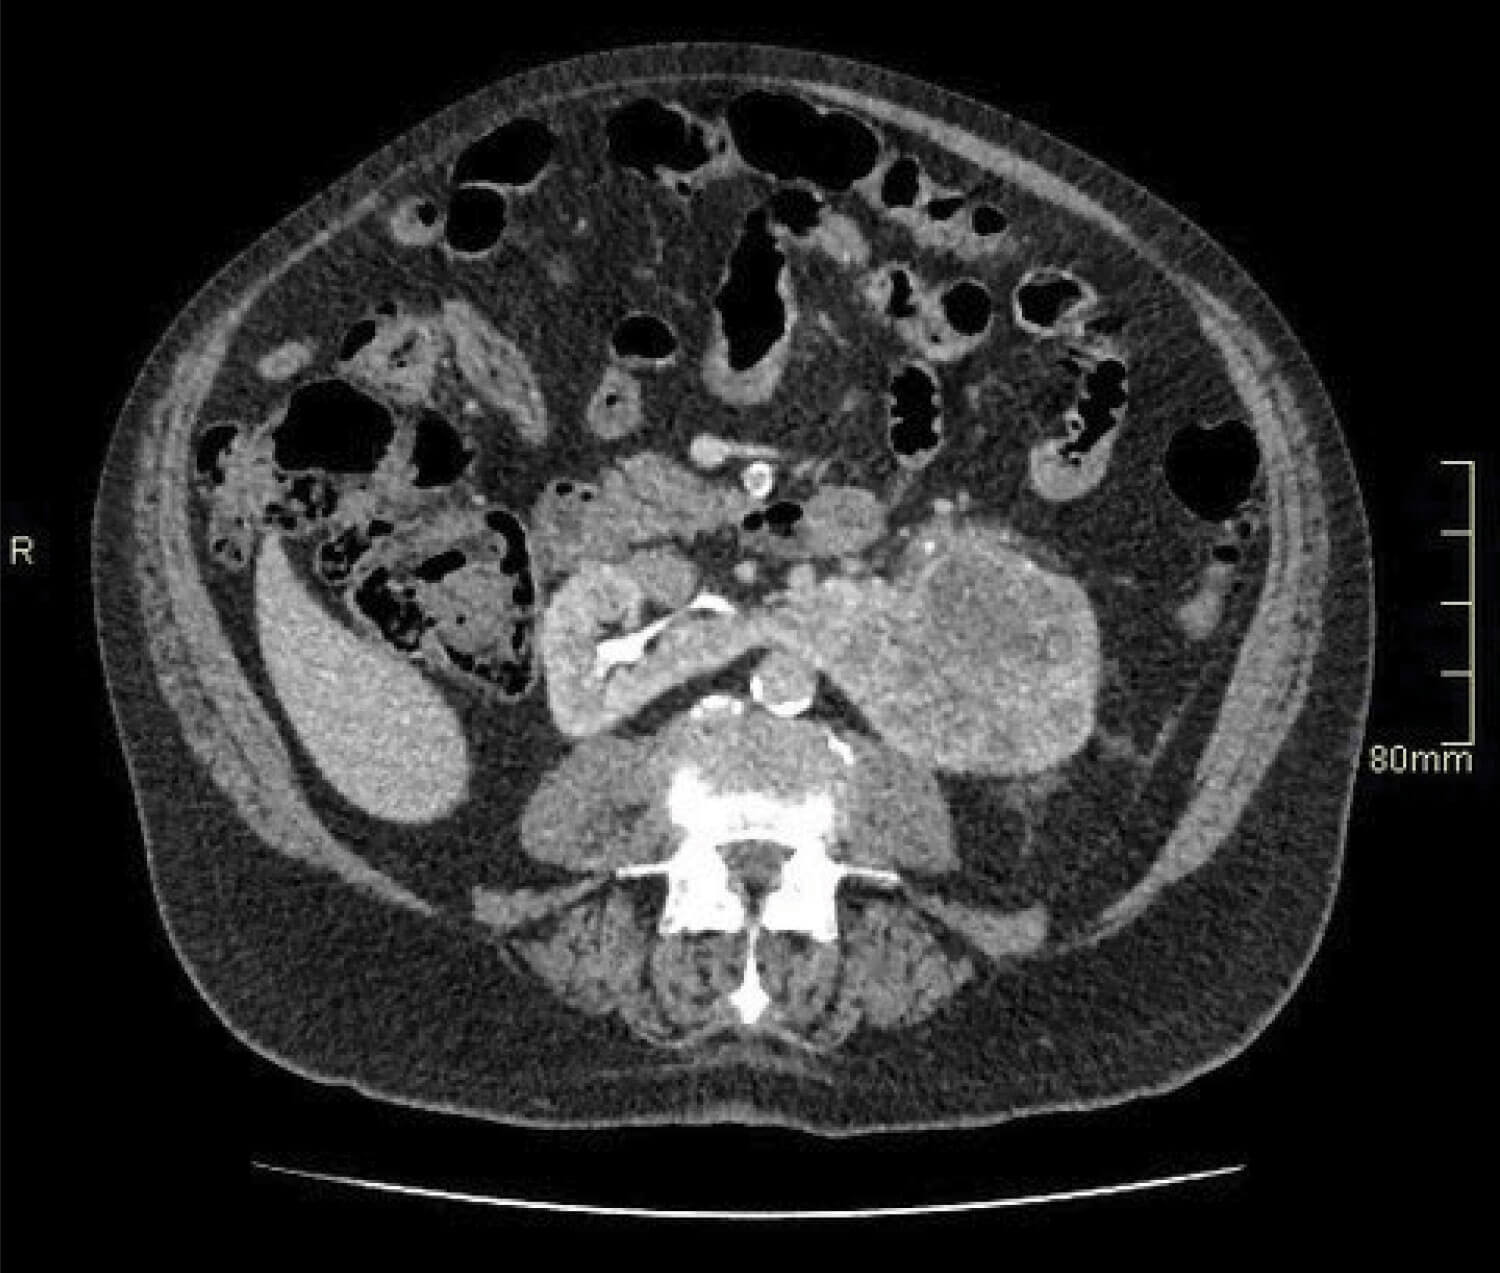

Figure 2.

- An 82-year-old man presents with visible haematuria. Flexible cystoscopy is normal, but what does the contrast CT image in Figure 2 show?

- The image shows an 8cm tumour in the left moiety of a horseshoe kidney.

- This tumour is T2a at least given the size visible here: further images would reveal invasion of the renal vein, T3a.

- Horseshoe kidney is associated with an increased risk of renal malignancies including renal cell carcinoma, transitional cell carcinoma (three times), Wilm’s tumour (twice as likely) and an extremely large increase in very rare tumours such as Carcinoid (62 to 82 times) [3]. Horseshoe kidneys are rarely associated with PKD, with fewer than 20 cases reported: the risk of having both is estimated to be 1:8,000,000 [6].

- Imaging with arterial phase contrast is useful prior to surgery for renal tumours, to detect relevant vascular anomalies - which are more common in horseshoe kidney. It is also useful to assess renal function in the unaffected moiety, for which a DMSA scan would be ideal [1,2].

- A heminephrectomy is the definitive surgical management for a tumour of this size in a horseshoe kidney.6. T3a, Nx, Mx, and Leibovich score 8 (high risk) [7].